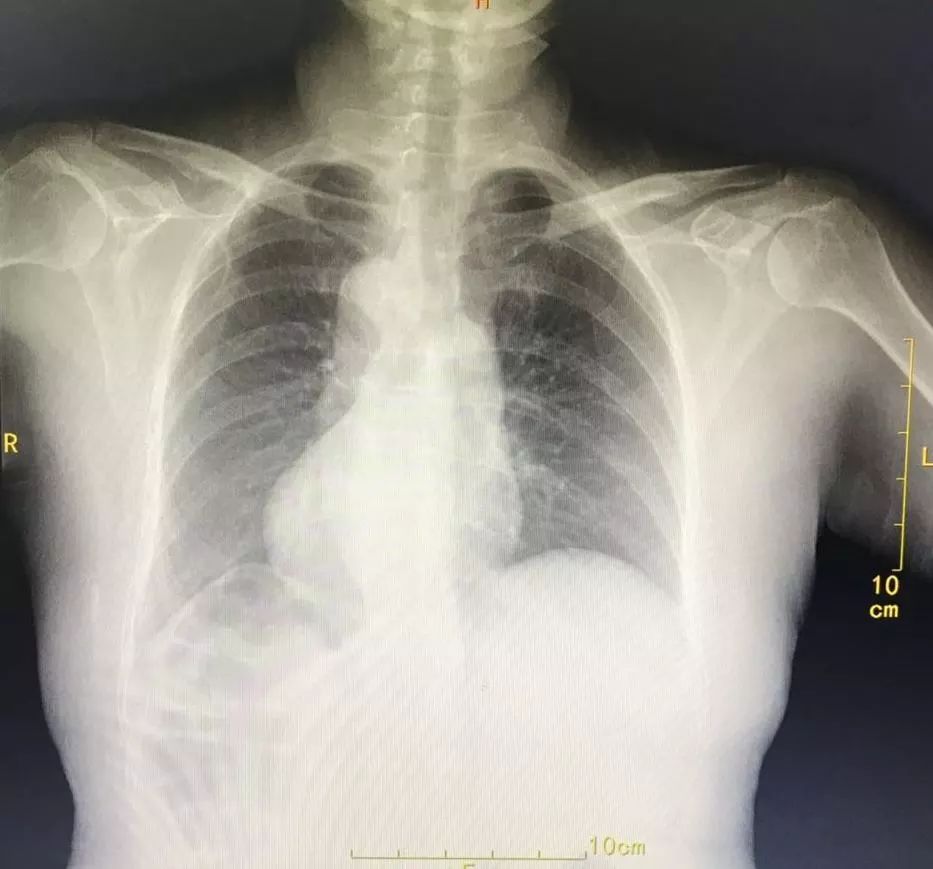

患者的影像结果显示,心脏位于右侧

CT提示:全内脏反位